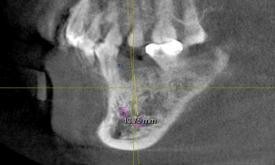

专科检查:下颌乳Ⅴ滞留,松动Ⅲ度。x线片检查:35先天缺失。下颌乳Ⅴ牙根吸收到牙颈部。

处理:(1)拔除下颌乳Ⅴ。(2)一个月后行种植修复。

本病例即刻种植也可以,但考虑软组织的情况,建议一个月后软组织愈合后种植,愈合基台周围的软组织封闭要比即刻种植要好。